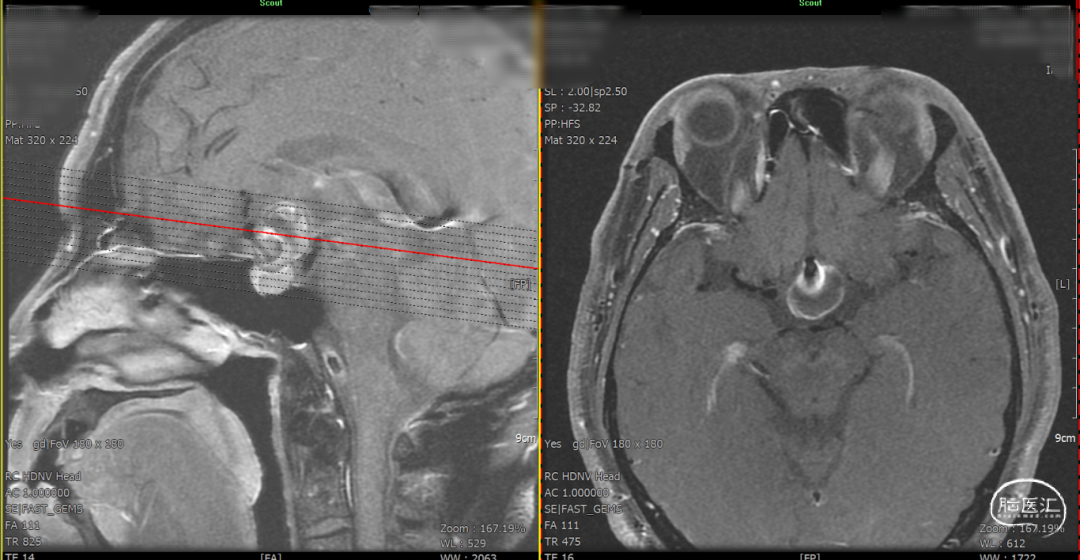

DSA造影3D重建测量

拟行脑动脉瘤密网支架置入术。

2.5mm*15mm Surpass Evolve密网支架,支架锚定区为右侧A2~A1

顺利建立通路,在输送支架到位过程中,XT-27保持稳定。

造影确认远端打开良好,定位后完全释放支架。

支架置入后造影显示,瘤内滞留明显,对侧造影几乎未见瘤内造影剂显影,手术结果满意。